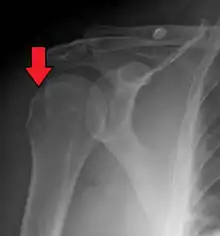

| Anterior shoulder dislocation on X-ray with a large Hill–Sachs lesion | |

A Hill–Sachs lesion, or Hill–Sachs fracture, is a cortical depression in the posterolateral head of the humerus. It results from forceful impaction of the humeral head against the anteroinferior glenoid rim when the shoulder is dislocated anteriorly.

Diagnosis can be suspected by history and physical examination which is usually followed by imaging. Because of the mechanism of injury, apprehension of anterior dislocation is common with provocative maneuvers. Hill–Sachs lesions have been classified as "engaging" or "non-engaging", with engaging lesions defined by the ability of the glenoid to sublux into the humeral head defect during abduction and external rotation. Engaging dislocations have a higher risk of recurrent anterior dislocation, and their presence can help guide surgical management.[2] Imaging diagnosis conventionally begins with plain film radiography. Generally, anteroposterior (AP) radiographs of the shoulder with the arm in internal rotation offer the best yield while axillary views and AP radiographs with external rotation tend to obscure the defect. However, pain and tenderness in the injured joint make appropriate positioning difficult and in a recent study of plain film x-ray for Hill–Sachs lesions, the sensitivity was only about 20%. i.e. the finding was not visible on plain film x-ray about 80% of the time.[3]